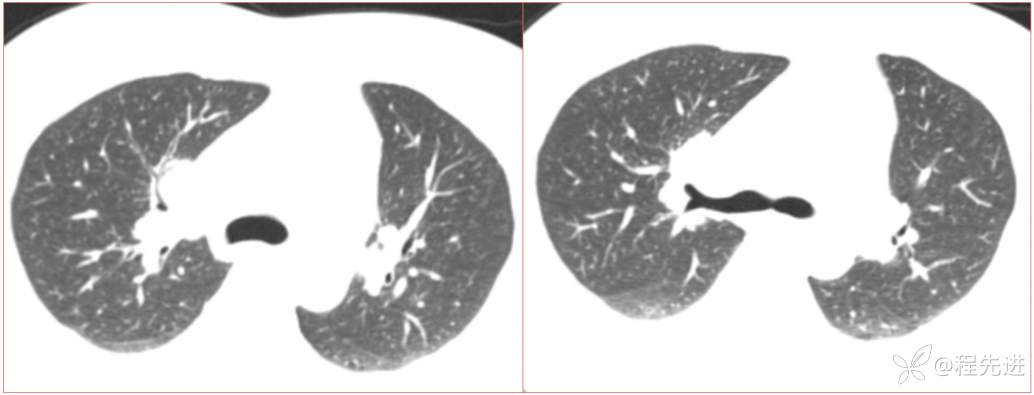

简要病史:患者一周前无明显诱因出现阵发性刺激性咳嗽,咳少量白色粘液痰,咳嗽无明显昼夜节律性,无发热、畏冷、寒战,无头痛、胸闷、胸痛,自行服药后 (具体不详) 症状无缓解,3天前外院胸片检查示右上病变

辅助检查:肺肿瘤标志物:神经元特异性烯醇化酶(NSE):35.72ng/ml(参考值0-16.3);非小细胞肺癌相关抗原211、胚抗原糖类抗原125、铁蛋白、鳞状细胞癌抗原未见异常